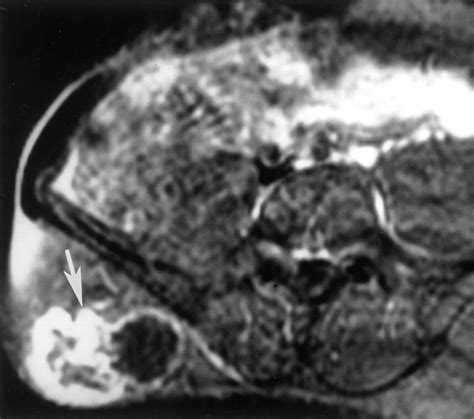

If you suspect you have a nerve sheath tumor, your doctor will likely begin with a physical examination to test your reflexes, muscle strength, and sensory perception. Following this, imaging studies are the gold standard for confirming the presence and size of the growth.

Magnetic Resonance Imaging (MRI) Provides high-resolution images of soft tissues, ideal for visualizing nerves.